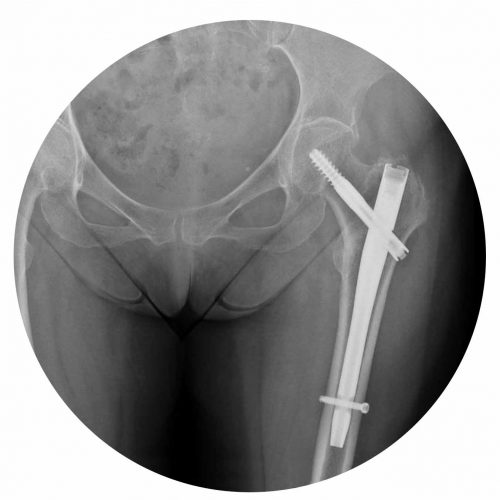

Osteosynthesis of Femoral Neck Fractures

Osteosynthesis of femoral neck fractures consists of fixing the fracture with screws or plate and screw system in order to allow subsequent bone healing.